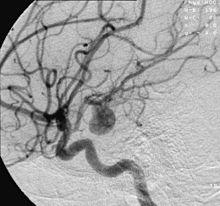

Aneurysm in a cerebral artery,

one cause of hypoxic anoxic injury (HAI).

2. Focal cerebral ischemia – A stroke occurring in a localized area that can either be acute or transient. This may be due to a variety of medical conditions such as an aneurysm that causes a hemorrhagic stroke, or an occlusion occurring in the affected blood vessels due to a thrombus (thrombotic stroke) or embolus (embolic stroke).[20] Focal cerebral ischemia constitutes a large majority of the clinical cases in stroke pathology with the infarct usually occurring in the middle cerebral artery (MCA).[21]